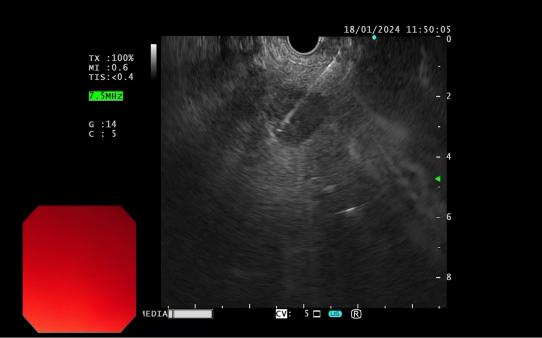

發現內源性低回聲病灶 實時超聲引導下對病灶的細針穿刺活檢

內鏡超聲引導下細針穿刺抽吸術(EUS-FNA):治療對于性質不明的胰腺實性占位性病變;對于經CTMRI或 EUS 等檢查不能確定性質的胰腺囊性病變;對于消化道毗鄰組織中性質不明的占位性病變或淋巴結腫大(如縱隔、上腹部等部位病變);長徑>2cm需要手術切除但具有高手術切除風險,或不能切除的消化道上皮下腫瘤的鑒別診斷。